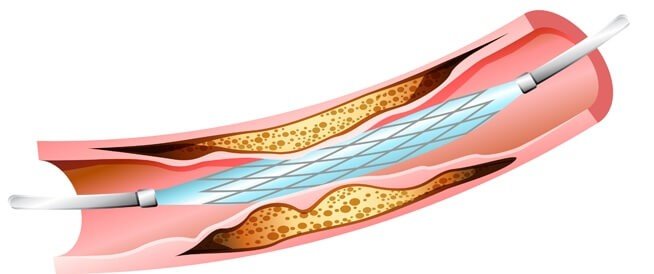

ما هو شكل القسطرة القلبية ؟

القسطرة القلبية عبارة عن أنبوب رفيع مجوف ويكون مرن يسمى (القسطرة) ويتم توجيهه عن طريق الأوعية الدموية، إما في الذراعين أو الفخذ أو اليد، وذلك لأخذ صور بالأشعة السينية للشرايين التاجية التي توصل الدم إلى عضلة القلب، وذلك الأنبوب يسمى أيضاً “قثطرة القلب، تصوير الشرايين التاجية”.

إذا وجد الطبيب مشاكل في القلب والشرايين التاجية، يقوم بإجراء عملية القسطرة القلبية العلاجية، وبالنسبة إلى شكل القسطرة القلبية العلاجية لم يختلف عن التشخيصية، وذلك النوع عبارة عن علاج غير جراحي يستخدم لفتح الشرايين التاجية الضيقة لتحسين رؤية القلب، ويمكن إجراؤه في نفس موعد إجراء القسطرة القلبية التشخيصية، أو قد يتم تحديد موعده آخر، وذلك بوضع بالون مع وضع الدعامة إذا احتاج المريض لذلك.

شكل القسطرة القلبية التشخيصية لا يختلف عن شكل القسطرة القلبية العلاجية، حيث أن القسطرة العلاجية تشبه القسطرة التشخيصية، حيث أن القسطرة العلاجية يتم فتح الشرايين التي تكون مسدودة وذلك بواسطة أسلاك دقيقة داخل الشرايين عبر القسطرة ( شكل القسطرة القلبية ) وبعدها يتم توسيع التضييق عن طريق بالون صغير أو بواسطة دعامة، وتلك الدعامة إما تكون عادية أي مكونة من الشبكة المعدنية العادية، أو أن تكون دوائية، وذلك العلاج يتم دون تخدير عام ودون فتح للصدر بل عن طريق فتحة صغيرة في الشريان الفخذى الأيمن أو الذراع أو اليد، وتلك الفتحة لا تتجاوز أل 2 مليمتر.